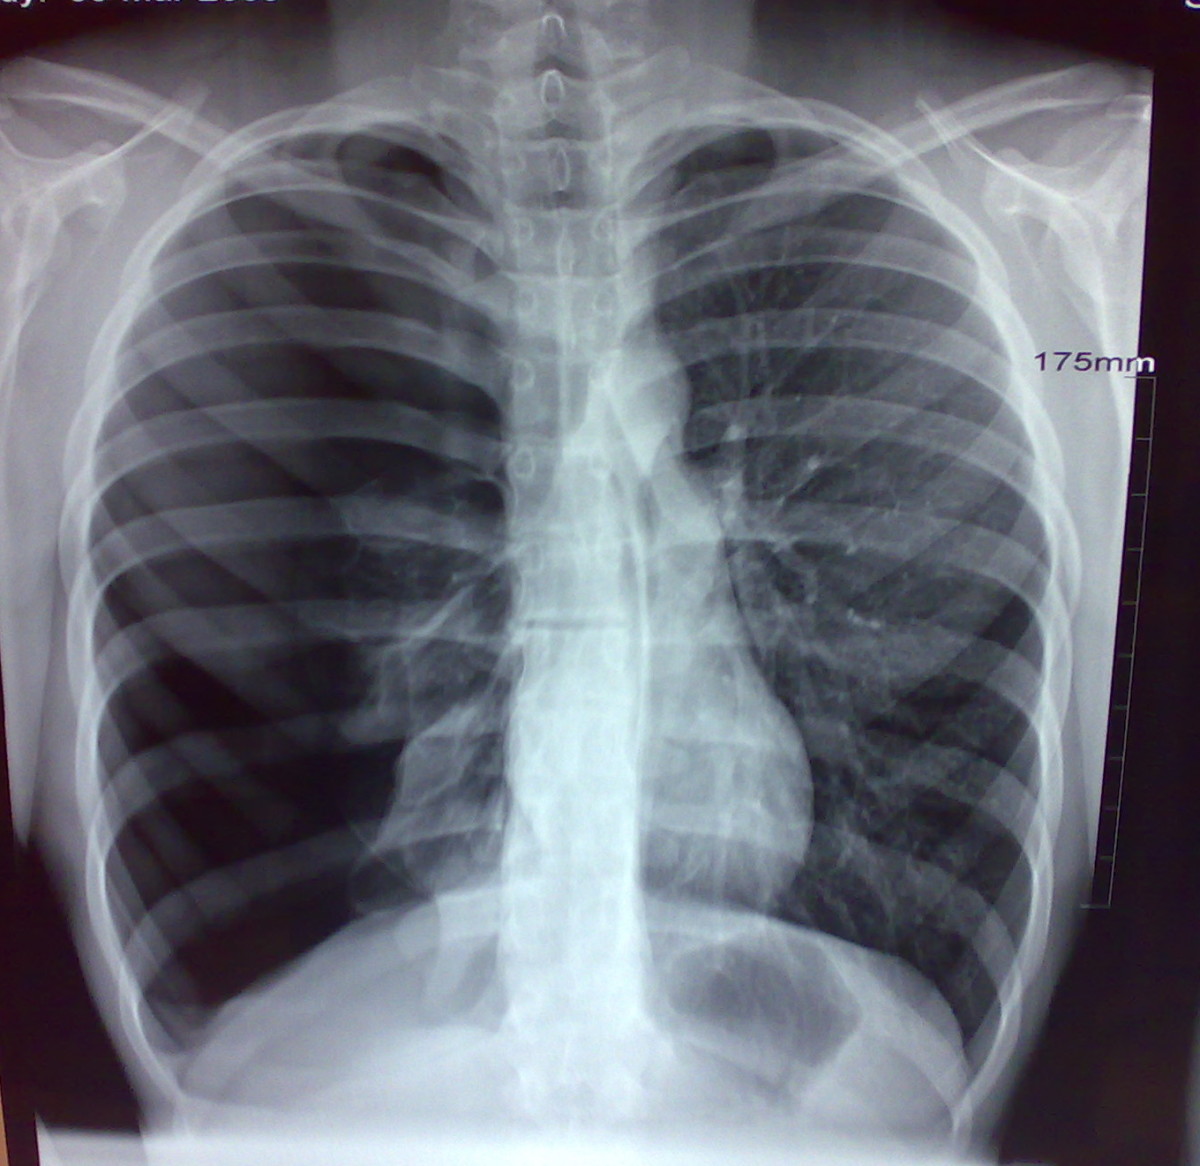

X Ray Diagnostics Of Pneumothorax Radiographic Representations Of The Blast Chest Injury Bombs and explosions can cause unique patterns of injury seldom seen outside combat. Injury from blast is due to compression and disruption of tissues by a shock wave that lasts for milliseconds, with damage occurring where. Apnea, bradycardia, and hypotension are the clinical triad classically associated with blast lung injury. Expect half of all initial casualties to. Tympanic membrane rupture. Blast Chest Injury.

(PDF) Blast InjurIes AACHCBlast InjurIes Blast Lung Injury Photo Blast Chest Injury The primary blast mechanism causes. Expect half of all initial casualties to. Apnea, bradycardia, and hypotension are the clinical triad classically associated with blast lung injury. Tympanic membrane rupture has been. Bombs and explosions can cause unique patterns of injury seldom seen outside combat. Injury from blast is due to compression and disruption of tissues by a shock wave that. Blast Chest Injury.